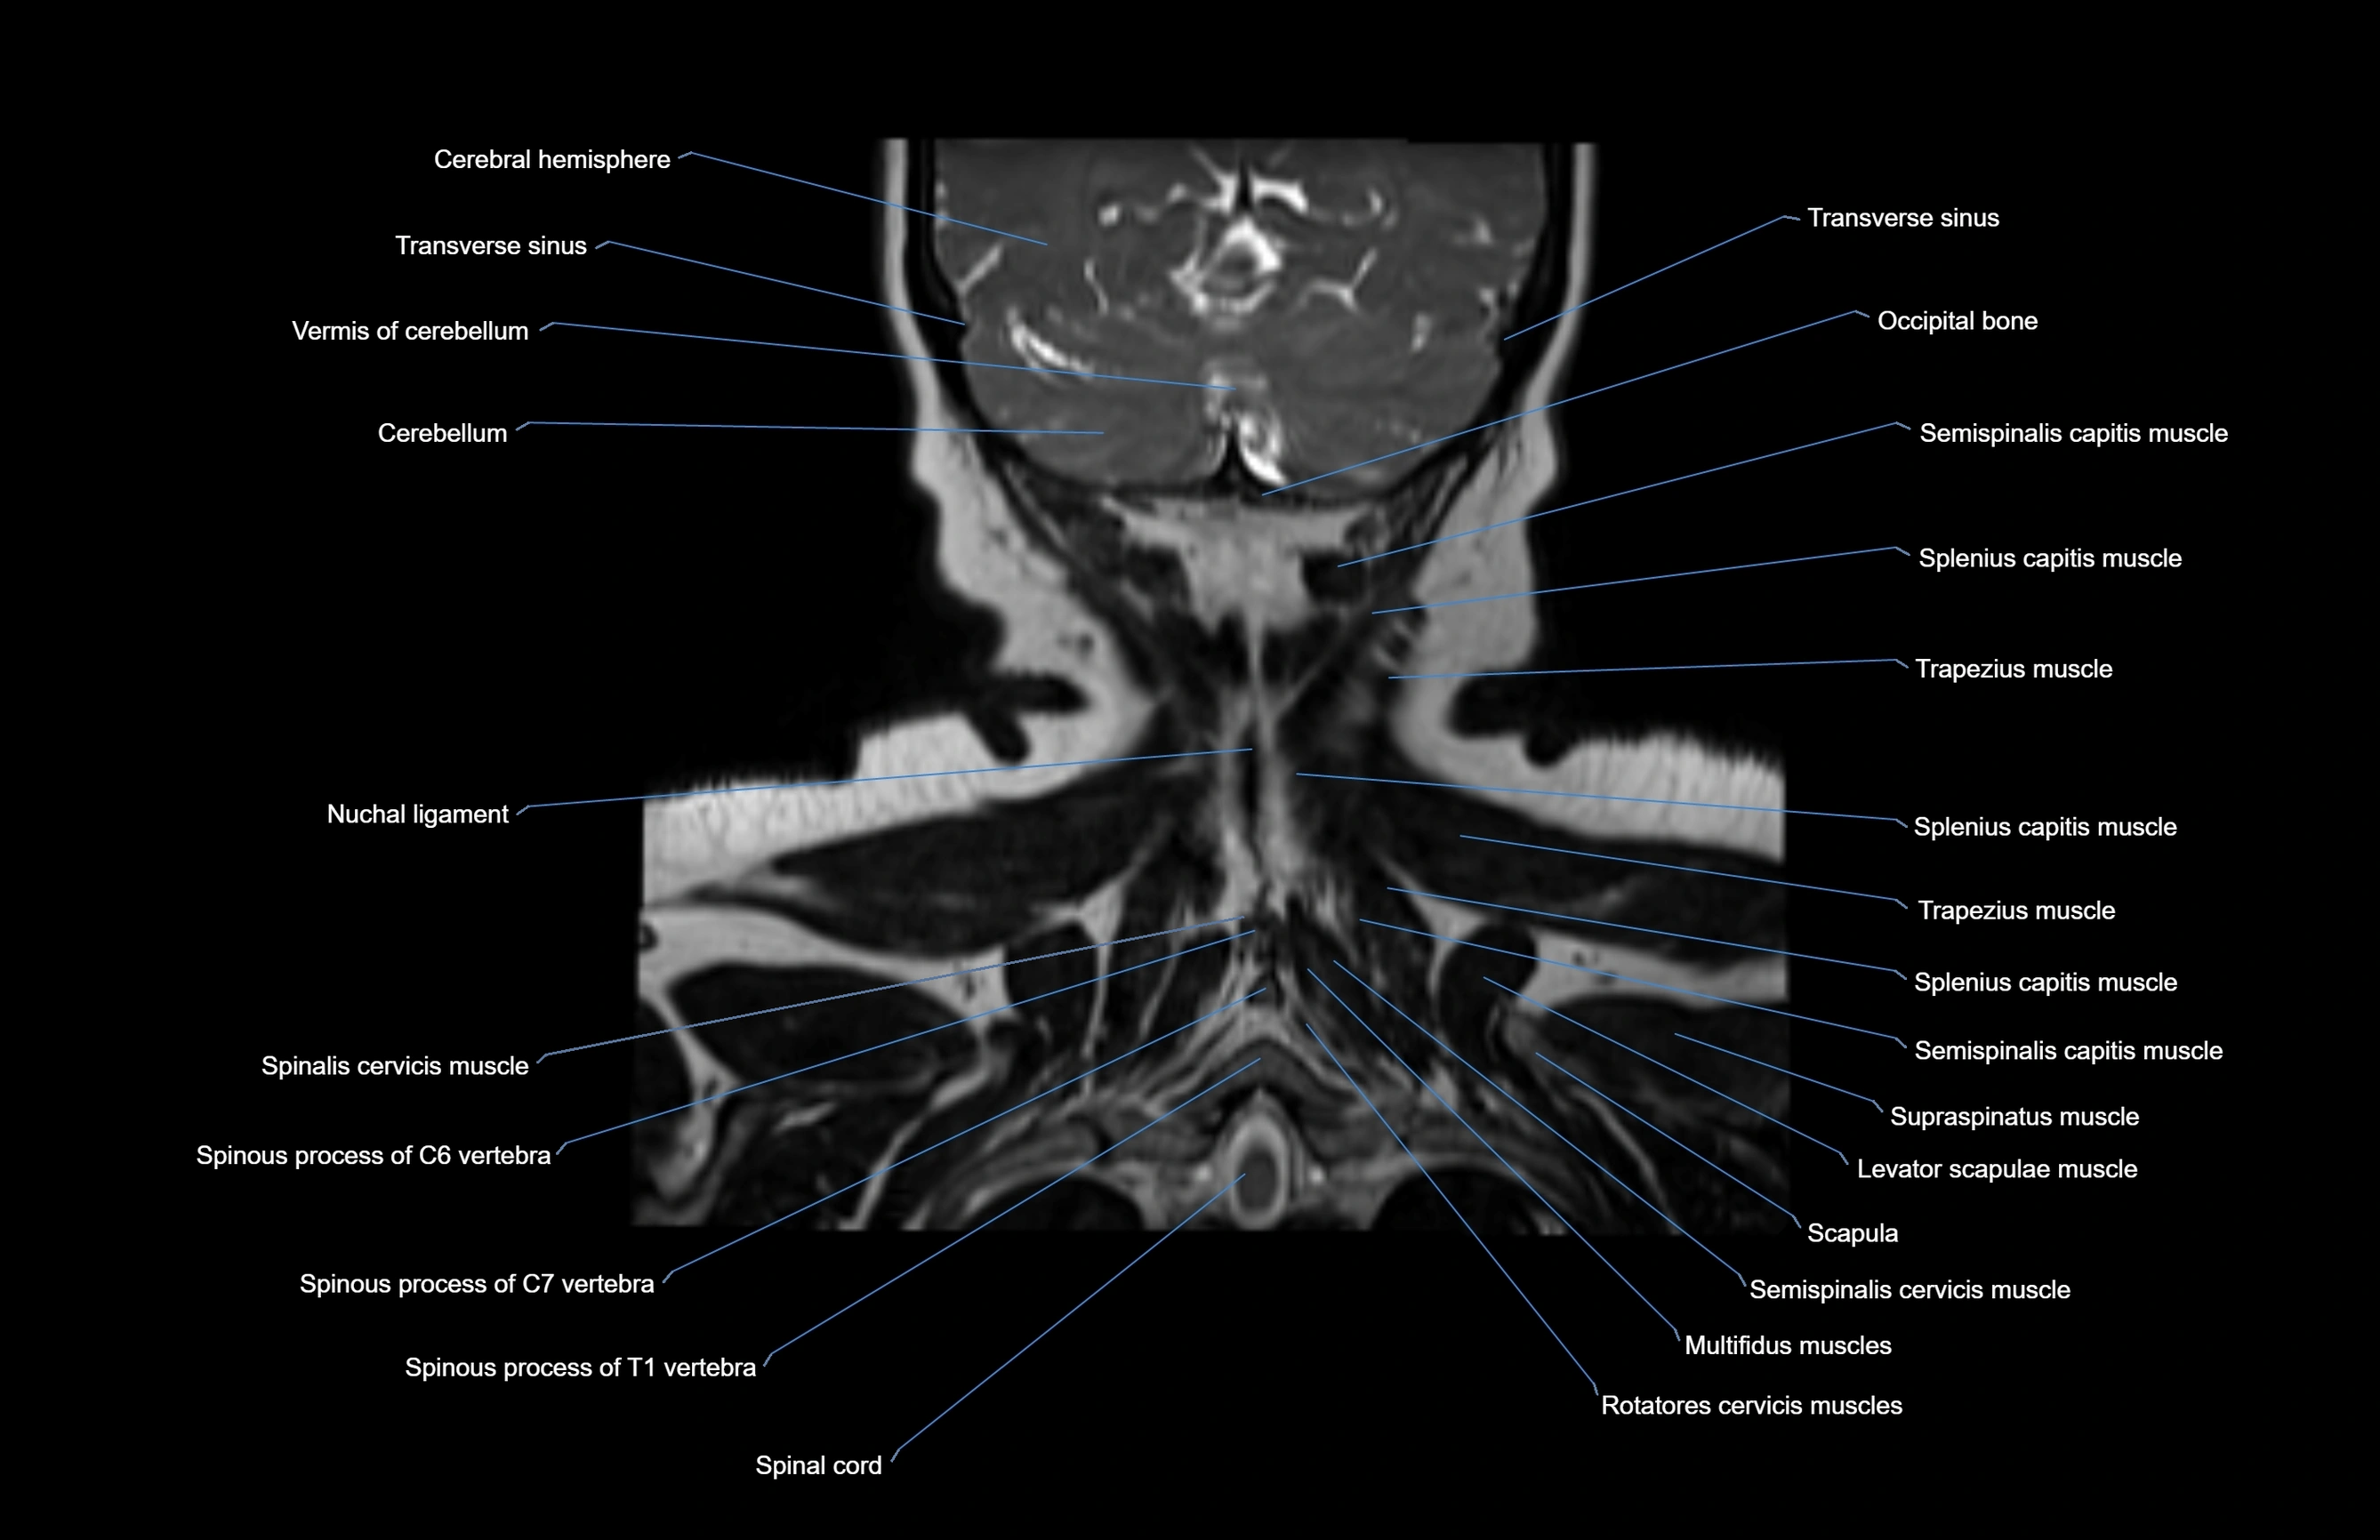

MRI images